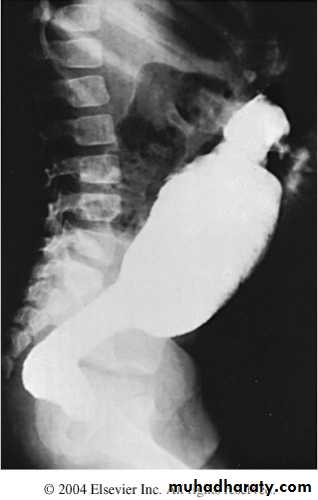

What is the differential diagnosis?Timing of operation?A 4 week old boy presents with vomiting. The pictures show the investigation and the operative findings.1. What is the diagnosis ?2. What is the investigation shown in slide A ?3. How do you treat ?4. What is the character and contents of vomitig in this pathology?5. What are the other methods of diagnosis?

A 2 week old boy presents with history of constipation, abdominal distension and bilious vomiting. The pictures show the operative findings and radiographic investigation done for him.1. What is the diagnosis?2. What is the underlying pathology for this condition?3.Describe the findings in all slides.4. What other investigations used to reach the diagnosis?5. What are the steps of management for this condition?